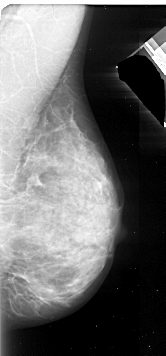

A_1092_1.LEFT_MLO

LEFT_MLO LINES 5536 PIXELS_PER_LINE 2431 BITS_PER_PIXEL 16 RESOLUTION 42 OVERLAY